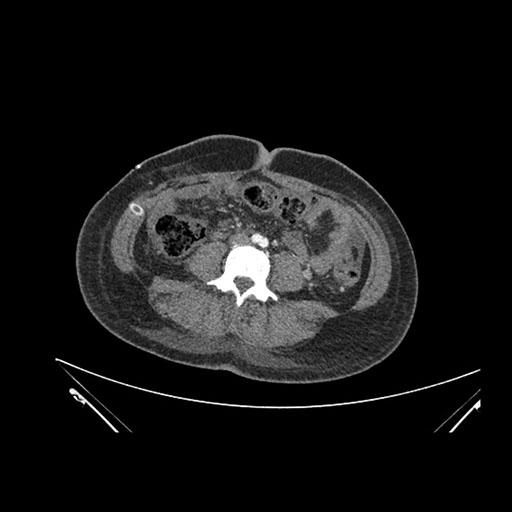

Axial Arterial

Imaging analysis

Based on initial findings, which issue(s) would you be most concerned about?